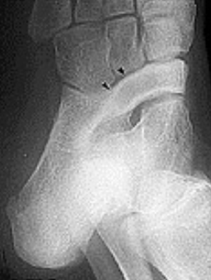

| What is this? What is shown by A and B? | STJ coalition A = talar neck spurring B = Halo or 'C' sign |